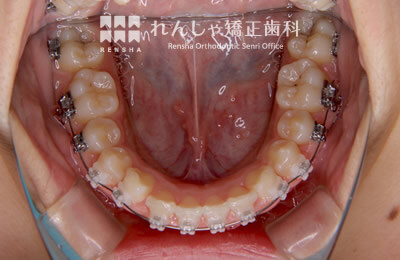

中高生

永久歯列はほぼ完成してしますが、歯列を側方だけでなく後方へも拡大し、埋まっていた右上奥歯を引っ張り出しています。

治療前

治療中

治療後

| 主訴 | 埋まったままでてこない歯がある |

|---|---|

| 診断名 | Angle Class II 小臼歯の埋伏と叢生を伴う上顎前突 |

| 初診時年齢 | 13歳5か月 |

| 装置名 | マルチブラケット装置 |

| 抜歯非抜歯 | 非抜歯 |

| 治療期間 | 2年3か月 |

| 費用の目安 | 約82万円+消費税(検査料金、都度の処置費用等も合わせた総額) |

| リスク副作用 | 歯の移動に伴う軽微な歯根吸収、歯槽骨吸収、歯肉退縮(本症例では軽度の歯根吸収を認めた)、矯正器具装着中のカリエスリスク増大(本症例ではカリエス発生無し) |